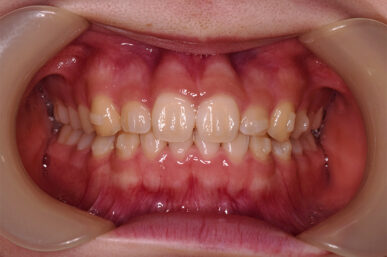

前歯のガタツキと隙間が気になる

Before

ライト1で治療しました。

前歯のみの問題で奥歯に問題がありませんでしたので、費用も期間も少なく治療できました。